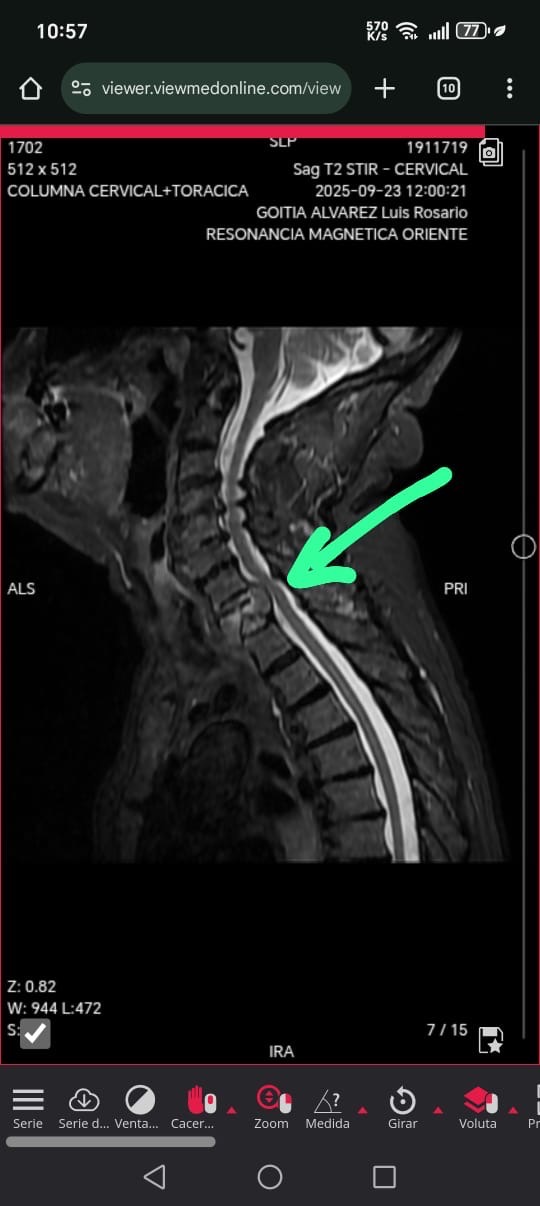

El pasado mes, la vida de Luis dio un giro inesperado. Tras una caída, sufrió una fractura en la vértebra T1 de su columna cervical. Esta lesión causó una compresión en la médula espinal, lo que le provoca dolores insoportables, pérdida casi total de movilidad y progresivamente capacidad de habla.

El único tratamiento viable es una cirugía de emergencia para evitar el riesgo inminente de de paraplejia . Aunque los médicos son optimistas, el camino hacia la recuperación será largo y costoso.